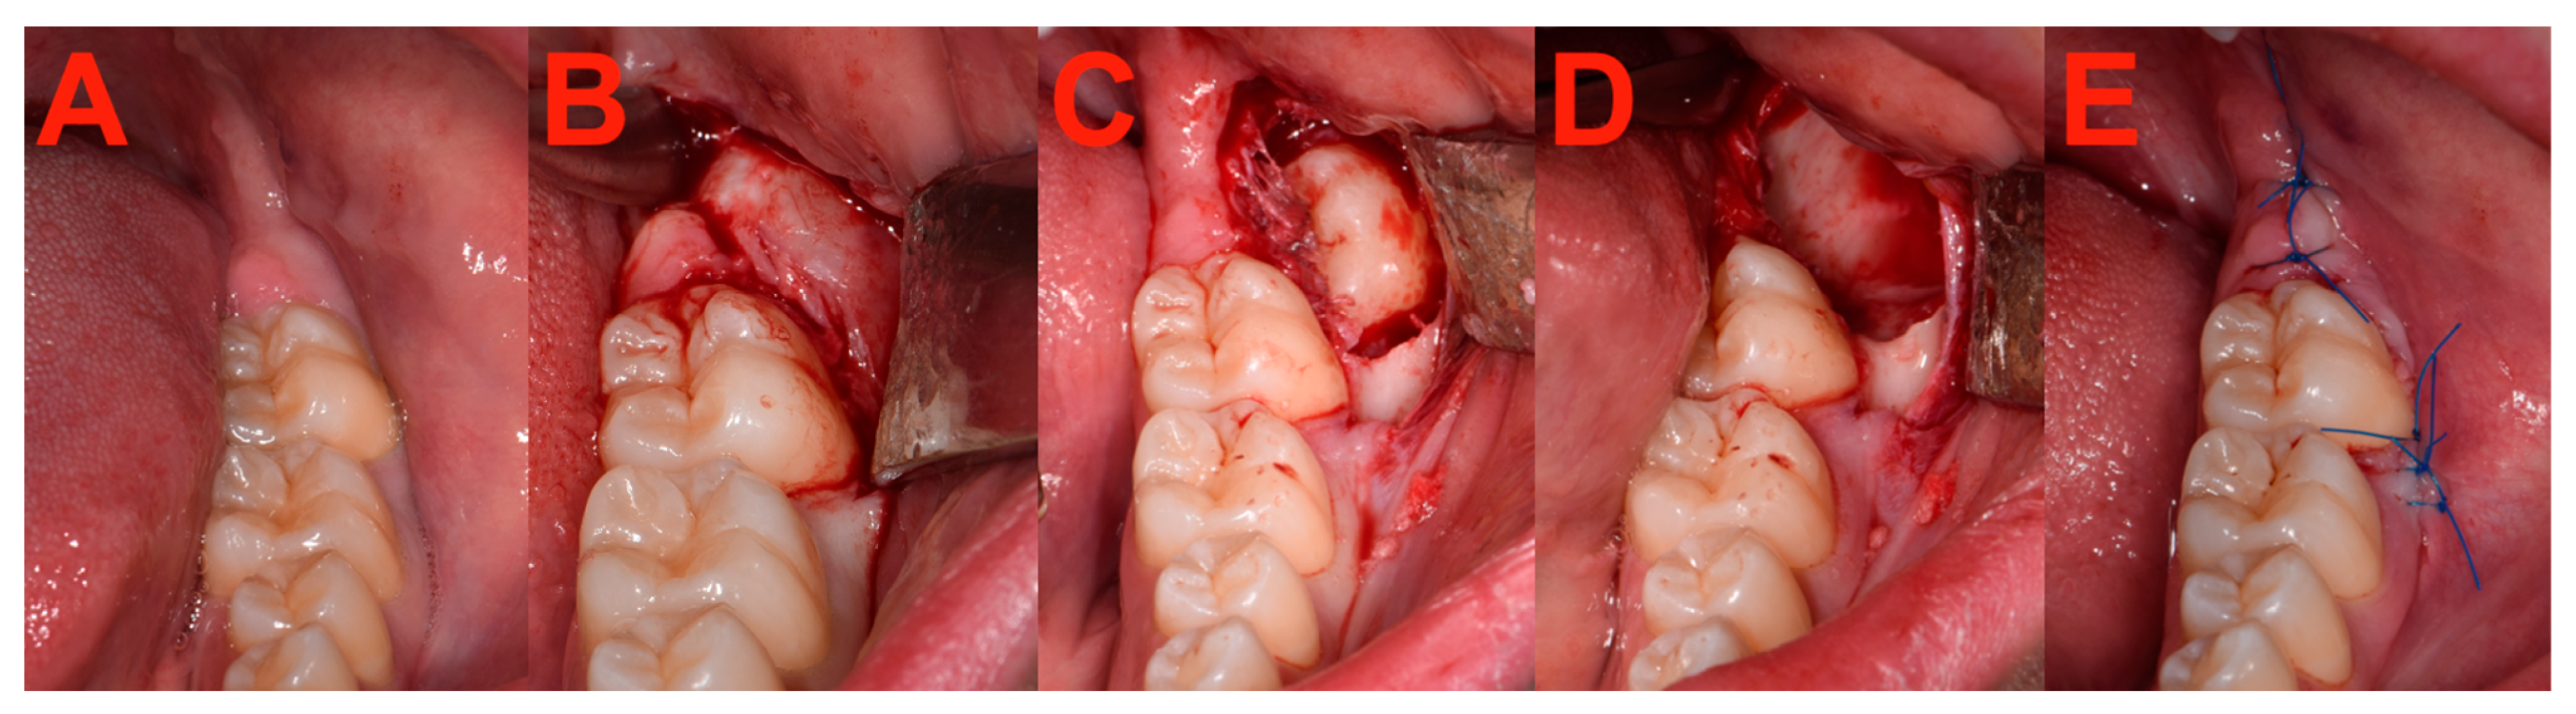

2.7. Surgery

2.8. Measurements